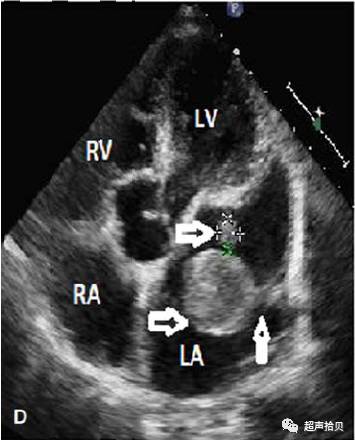

D,两个圆形肿块在左心房发现;有蒂(箭头指示粘液瘤)。

右心室;右心房;左心室;LA;左心房;AO,主动脉。